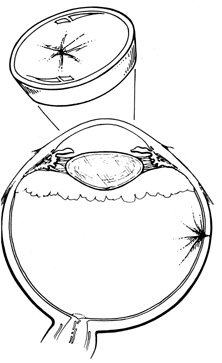

One result of circumferential encircling scleral buckles is fish-mouthing of retinal breaks.72,73 This is caused by the relative circumferential shortening of the sclera and choroid induced by the buckle in relation to the retina. This relative excess of retinal surface causes the retina to lie in radial folds over the buckle. These folds, in conjunction with vitreous traction, can result in the failure of retinal breaks to settle over the buckle. The breaks may form an elongated oval configuration in the anteroposterior meridian over the buckle, resembling the open mouth of a fish (Fig. 23). Persistent elevation of the retina resulting from the fishmouth phenomenon can result in surgical failure and therefore needs to be addressed.

Fig. 23. Fishmouth appearance after circumferential buckle.

There are three basic techniques in the management of fishmouth retinal tears. The easiest is to decrease the height of the circumferential buckle. This usually is effective only if buckle height is excessive. Placement of a radial element beneath the circumferential element effectively closes most fishmouth tears.69 The radial element increases the surface area of the pigment epithelium and choroid beneath the break, thereby decreasing the disparity between the retinal surface area and the surface area of the bed of the buckle (Fig. 24). 73 Injection of an intravitreal gas bubble, combined with appropriate positioning, also effectively closes fishmouth tears. The gas is injected through the pars plana under direct visualization with the indirect ophthalmoscope. During the injection, care must be taken to avoid formation of multiple small bubbles, which may then pass through the tear into the subretinal space. This can be prevented by injecting into the most superior aspect of the vitreous cavity. With accurate positioning, a bubble of 0.3 mL is adequate to close retinal breaks of up to one clock hour.74 The use of expansile gases, such as sulfur hexafluoride or perfluoropropane, can increase the intraocular volume of gas.

Fig. 24. Radial element beneath tear alleviating fishmouth phenomenon.